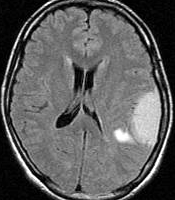

この髄膜腫は中程度の大きさのものです。円蓋部髄膜種という最も多い最も手術の簡単なタイプです。麻痺や失語症やてんかんなどの症状はありません。とても美しくて若い女性の髄膜腫でしたが,子供に遺伝はしませんし,癌などと違ってタバコなどこれといった原因がなくて発生するものです。

MRIでの髄膜腫の見え方は撮影の仕方によっていろいろです。左からT1強調画像,T2強調画像,フレア画像といいます。腫瘍の横に小さく白い領域がありますが,これは脳の腫れた部分で脳浮腫といいます。髄膜腫があると周囲に脳浮腫が生じることがあります。